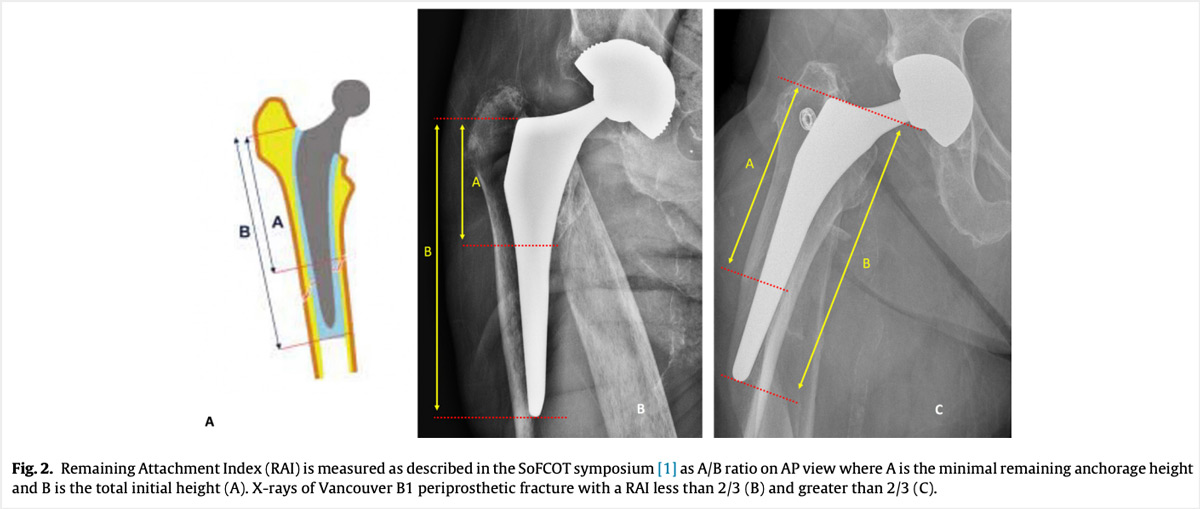

The French Society of Orthopedic Surgery and Traumatology (SoFCOT) recommended a specific Remaining Attachment Index (RAI) to asses residual fixation. Remaining Attachment Index < 2/3 in Vancouver B1 periprosthetic hip fracture is a risk factor for early implant loosening after isolated internal fixation

Remaining Attachment Index (RAI)

Andriamananaivo T, Odri GA, Ollivier M, Mattesi L, Renault A, Rongieras F, Pesenti S, Severyns M. Contribution of the remaining attachment index in the management of Vancouver B1 periprosthetic hip fracture. Orthop Traumatol Surg Res. 2020 Nov;106(7):1413-1417. doi: 10.1016/j.otsr.2020.06.016. Epub 2020 Oct 11. PMID: 33055000.